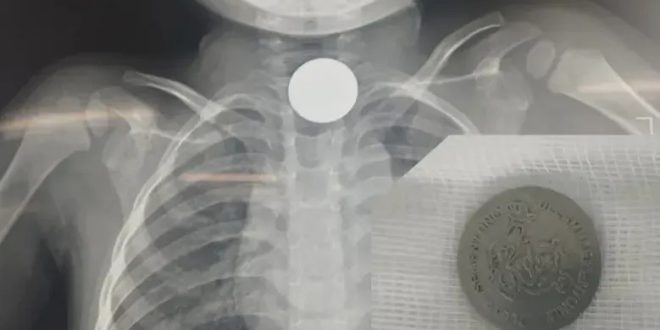

Sau khi thăm khám và chụp X-quang, các bác sĩ xác định có dị vật kim loại nằm trong thực quản của bé trai. Để giải quyết vấn đề này, các bác sĩ đã nhanh chóng tiến hành phẫu thuật nội soi để lấy dị vật ra khỏi cơ thể bé trai.

Bệnh viện Nhi Đồng Đồng Nai thành công trong việc gắp đồng xu ra khỏi thực quản bé trai 3 tuổi. Vụ việc xảy ra khi bé trai đùa giỡn và không may nuốt phải đồng xu vào trưa ngày 17/6. Ngay sau khi phát hiện sự cố, gia đình đã đưa bé trai đến Bệnh viện Nhi Đồng Đồng Nai để được cấp cứu.